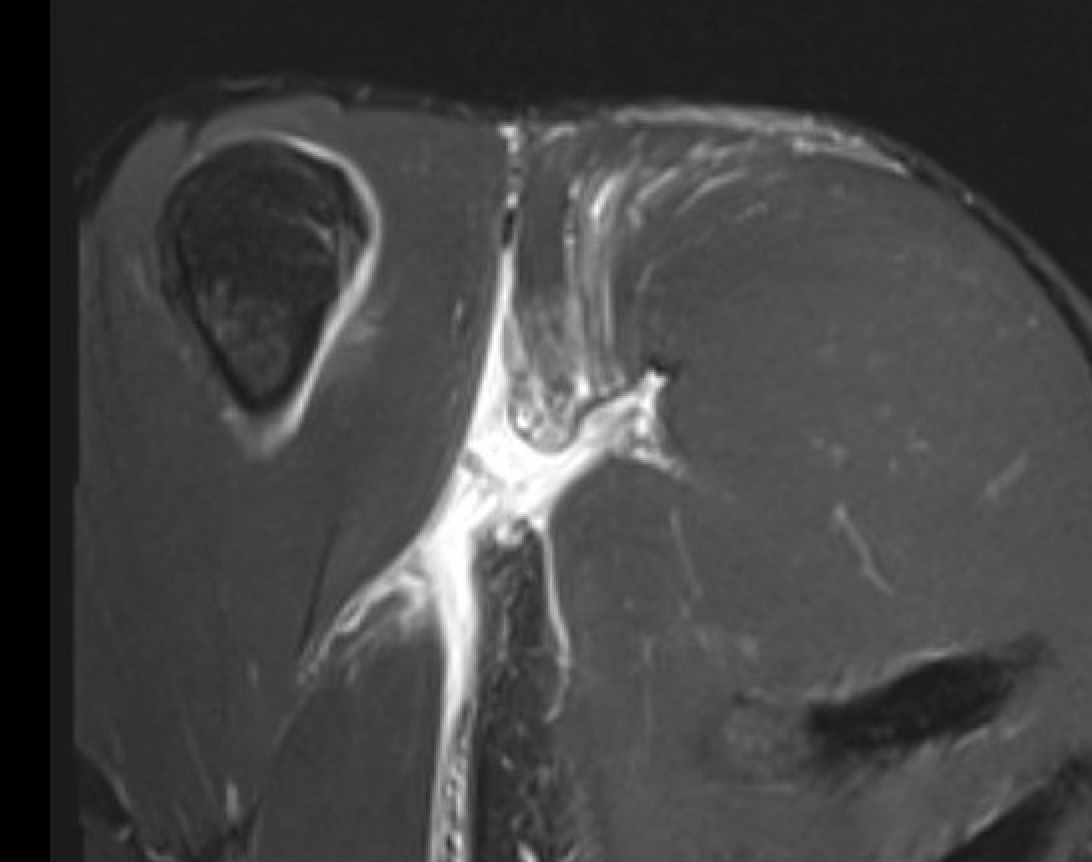

Coronal T2 MRI Right shoulder demonstrating musculotendinous avulsion